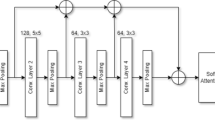

Brain tumors are one of the leading causes of death worldwide. Different types of brain tumors are known, so the choice of treatment depends directly on the type of tumor. The classification of brain tumors is very important as a complex and challenging problem in the field of image processing. Today, deep learning methods are used to classify brain tumors. In addition to being able to detect and automatically classify all types of brain tumors, these methods significantly reduce the diagnosis time and increase accuracy. In this paper, a deep learning-based model is proposed to classify brain tumors into three classes: glioma, meningioma, and pituitary tumor. In the first phase, the pre-trained network ResNet50 is used to extract features from MRI images. In the second phase, by proposing two attention mechanisms (depth-separable convolution-based channel attention mechanism and an innovative multi-head-attention mechanism), the most effective spatial and channel features are extracted and integrated. Finally, the classification phase is performed. Evaluations on the Figshare dataset showed an accuracy of 99.32%, which performs better than existing models. Therefore, the proposed model can accurately classify brain tumors and help neurologists and physicians make accurate diagnostic decisions.